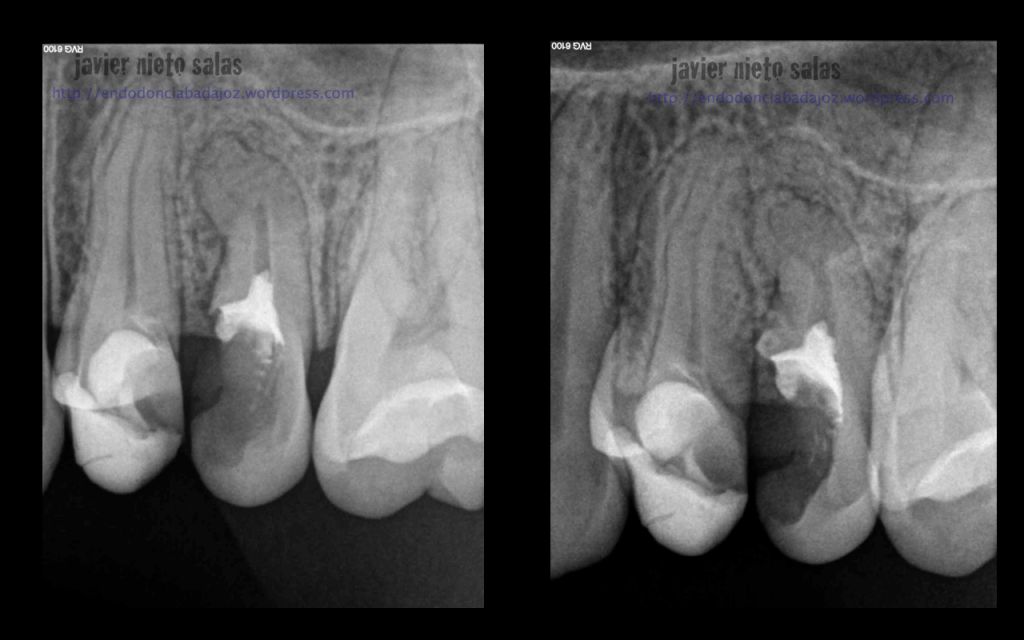

En el  primer caso de hoy, podemos ver la importancia de pararse a ver la radiografía inicial, el tamaño de la lesión y el posible origen, algo, a mi parecer, bastante importante.

Así pues, en esta primera imagen vemos la lesión lateral que nos hace sospechar de una posible salida a ese nivel. Modificando nuestra técnica de limpieza y obturación: